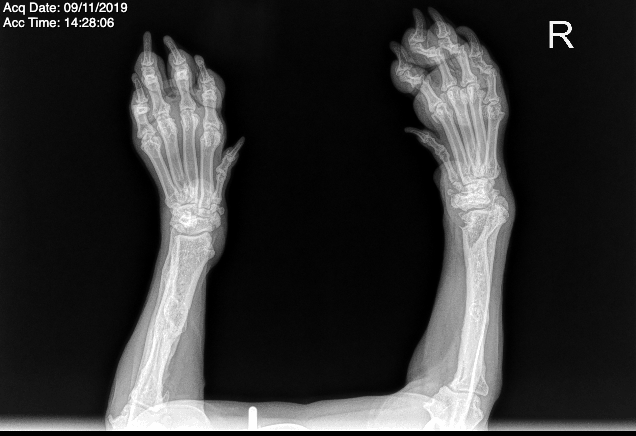

Angular Limb Deformities (ALD)

Angular limb deformities (ALD) are developmental conditions where a puppy’s leg grows at an abnormal angle rather than straight. They most commonly affect the front limbs and develop while the puppy is still growing.

Severity can range from mild cosmetic deviation to structural deformities that impact mobility and joint health.